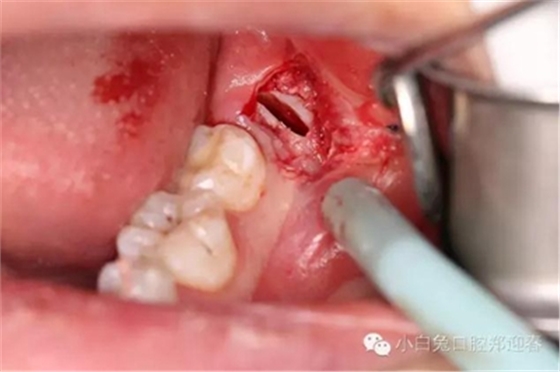

麻醉起效后,按照術(shù)前設(shè)計(jì),行粘膜切開翻瓣。

切口勿偏舌側(cè),頰側(cè)不要越過(guò)前庭溝,避免術(shù)后腫脹。

為了防止渦輪高速手機(jī)可能的組織纏繞,利用縫合線牽拉切開的瓣膜,充分暴露術(shù)區(qū)。